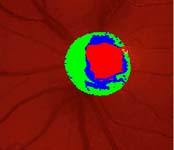

Očekávali byste protažení exkavace k hornímu pólu terče, jak nám ukazuje tento snímek z tomografu HRT II.

exkavace levé oko

Na kterém oku je exkavace větší, na pravém nebo na levém? Podle pohledu na fotografie jistě na levém.

Co je příčinou toho, že při pohledu na snímky hodnotíme rozsah exkavace nesprávně? Je to skutečnost, že i růžová oblast neuroretinálního lemu může být již prohloubená, což vídáme zvláště na počátku rozvoje glaukomové neuropathie.

A jak se můžeme vyhnout záměně okrsku bledší barvy za skutečnou exkavaci? Tím, že budeme mít na paměti, že exkavace může být větší než nablednutí. Také zařazení zeleného filtru na pomůže snížit nežádoucí barevný kontrast.